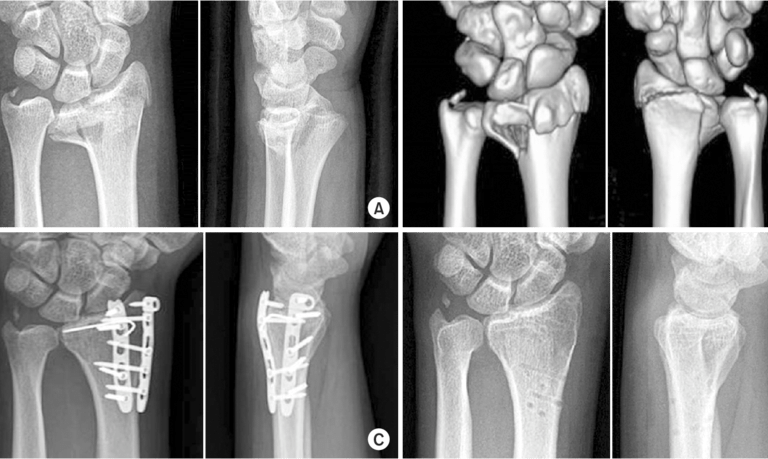

Radiografías: Son la herramienta principal para visualizar las fracturas de muñeca.

Tomografía Computarizada (TC): Puede proporcionar imágenes más detalladas si la radiografía no es concluyente.

Cuando las fracturas son complejas o están desplazadas, puede ser necesaria la cirugía:

Reducción Abierta y Fijación Interna (ORIF): Este procedimiento implica la colocación de placas y tornillos para mantener los huesos en su lugar.

Fijación Externa: Se utilizan pines y una estructura externa para mantener los huesos en su lugar.